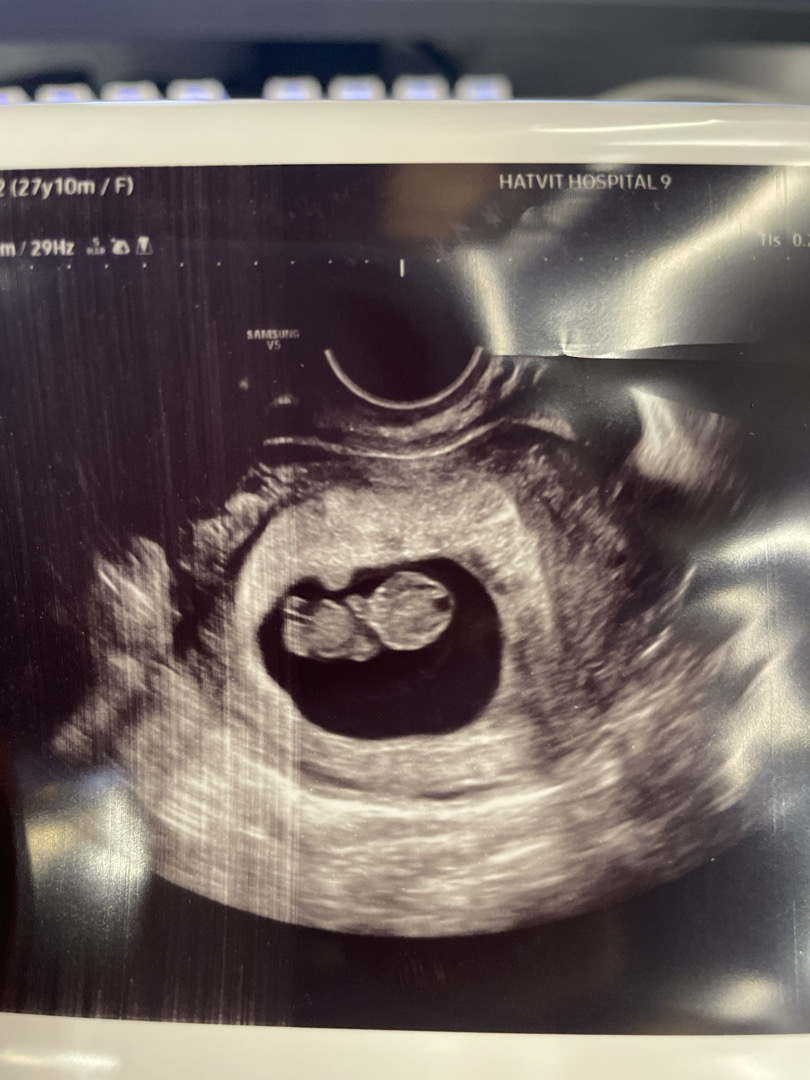

9주1일인데 움직이진 않을줄알았는데 움직이더라고요!! 진짜 넘 신기한거같아요 다들 9주차때문 젤리곰들 보셧나요!?머리가 많이 큰거같은데 그게 쫌 신경쓰이네욤 ㅜㅎ

젤리곰 귀여워욤!!ㅎㅎ 저두 젤리곰 보긴 했는데 촘파 화질이 안 좋아서 이쁜 젤리곰은 못봐서 아쉬워요우ㅜㅜ 머리 크기는 딱 2등신일 때라 제가 볼 땐 적당해 보이는걸요?!